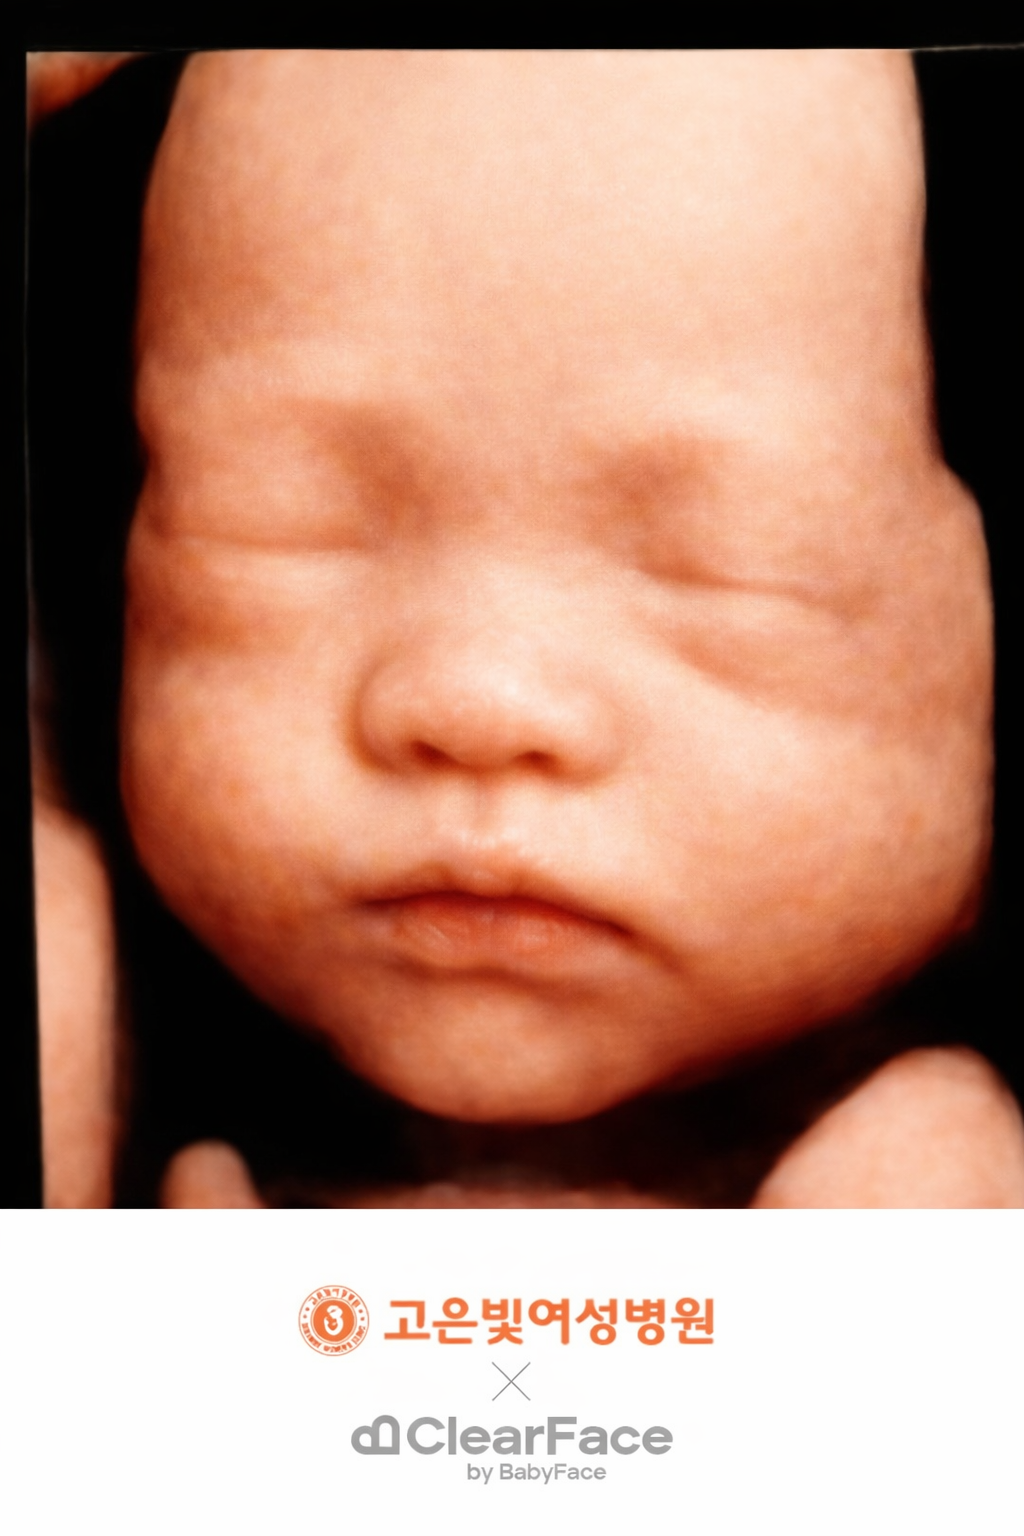

어느덧 임신 28주차, 입체초음파를 보고 왔습니다!

초음파 볼 때 마다 뽀동이가 얼굴을 잘 안보여줬어서 살짝 걱정했는데 아니나 다를까,,! 이날도 손과 발로 열심히 얼굴을 가리더라는,,,ㅎㅎ,,,,

초음파 봐주시는 선생님의 노력끝에 살짝 얼굴을 볼 수 있었어요!

이렇게 다섯장을 찍어주셨답니다!

이 중 마음에 드는 사진 한 장을 고르면 베이비페이스도 만들어줘요!

정말 뽀동이가 저렇게 생겼다면,,, 너무 귀여울 것 같아요!